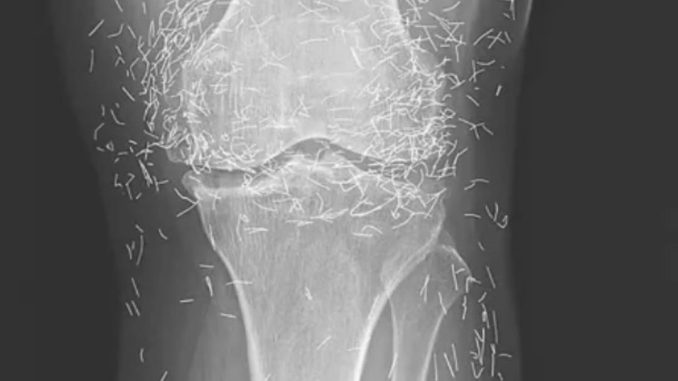

Doctors in South Korea were stunned when a routine knee X-ray of a 65-year-old woman revealed hundreds of tiny gold needles lodged deep in her tissue. She had been battling osteoarthritis for years, a condition that erodes cartilage and bone, leaving joints stiff, swollen, and painful.

In her case, the gold needles were intentionally left behind as part of her treatment, meant to deliver continuous stimulation to the affected areas.

A X-ray of the patient’s knee showing acupuncture needles embedded in the tissue, Photo Credit: Reddit

The risks don’t stop there. Needles can interfere with imaging, obscuring parts of the anatomy during X-rays. Even more concerning, patients with metal fragments in their bodies cannot undergo MRI scans. The strong magnetic force could shift the needles, puncturing blood vessels and causing life-threatening injuries.